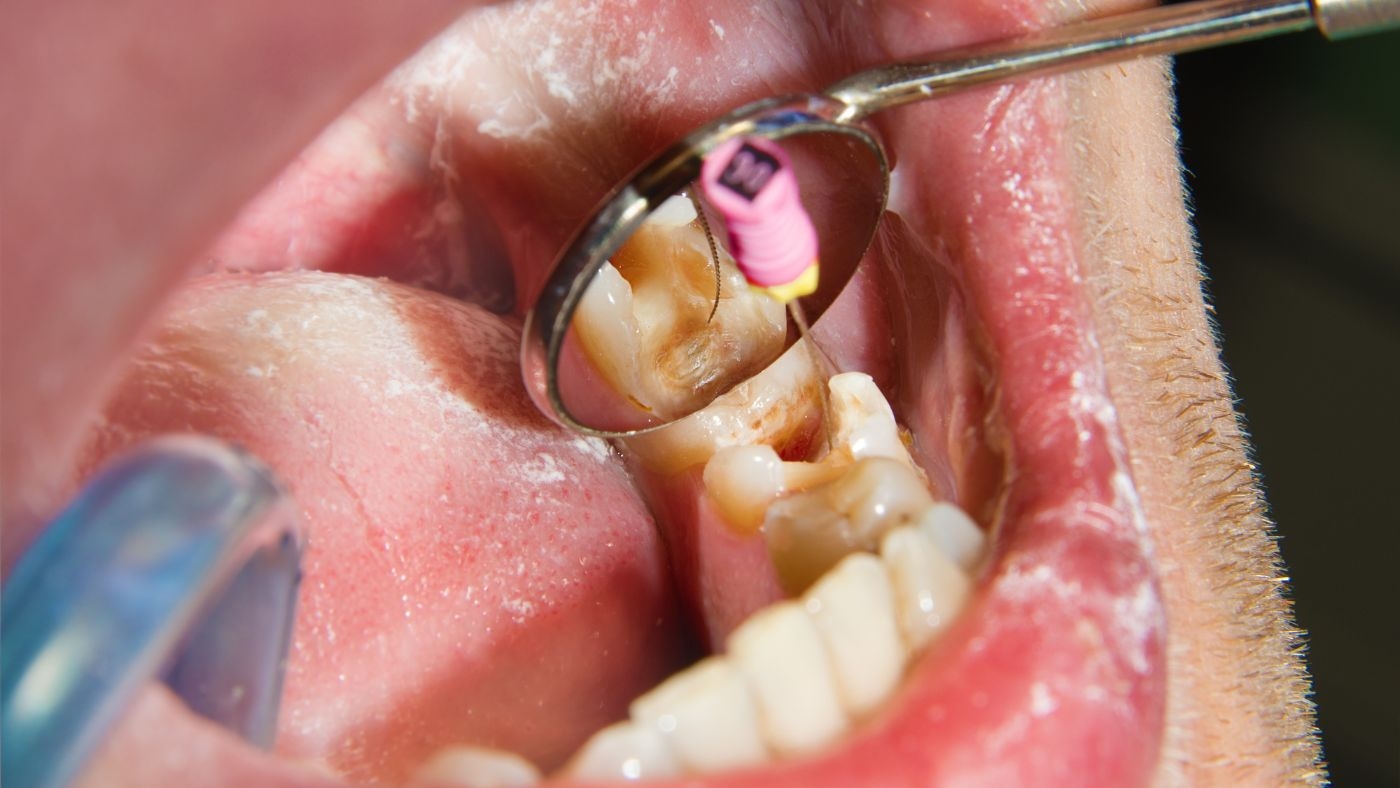

根幹治療の流れは、まず歯科医師が根幹内部の感染した組織を除去します。

その後、根幹内部を消毒し、清潔な状態を保つための治療を行います。

根幹治療では、根幹の形を整えながら、細菌を徹底的に取り除くことが重要です。

自由診療の根幹治療では、マイクロスコープという顕微鏡を使用した治療が一般的です。

マイクロスコープを使用することで、根幹内部を最大20倍以上に拡大して確認できます。

自費治療でのマイクロスコープ使用により、根幹治療の成功率が大幅に向上します。

ラバーダム防湿という技術も、自由診療の根幹治療では標準的に使用されます。

ラバーダムにより、治療中の根幹内部への唾液の侵入を完全に防ぐことができます。

自費治療では、ニッケルチタンファイルという柔軟性の高い器具を使用します。

このファイルにより、複雑な形状の根幹でも効率的かつ安全に治療できます。